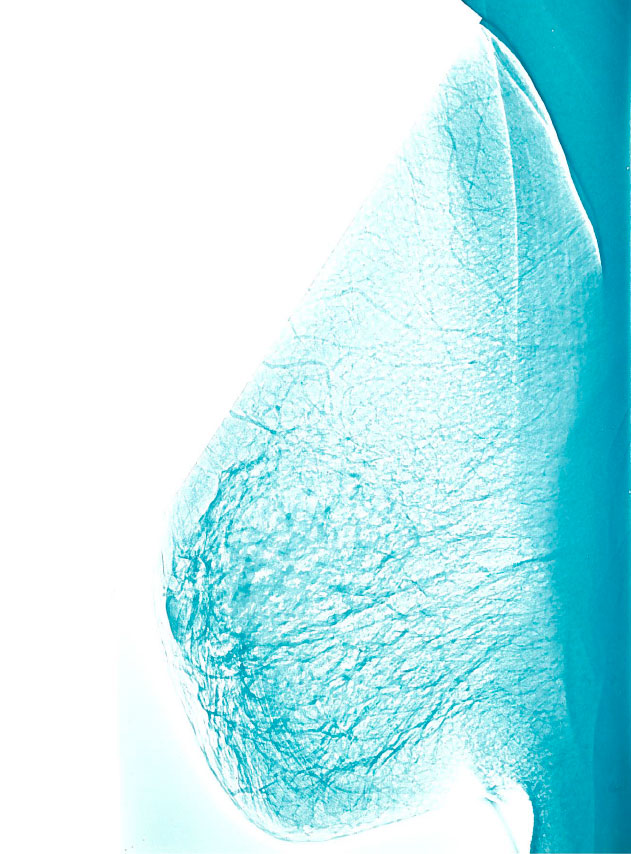

Nederland maakt op kleine schaal kennis met borstkankerscreening in Utrecht en Nijmegen. In deze steden starten in 1974 en 1975 twee proefbevolkingsonderzoeken.

In 1974 en 1975 gaan in Utrecht en Nijmegen twee proefbevolkingsonderzoeken van start. Daaruit blijkt onder andere dat een periode van vier jaar tussen twee uitnodigingen te lang is om borstkanker goed te kunnen opsporen in een vroeg stadium. In het bevolkingsonderzoek is die periode teruggebracht naar twee jaar.